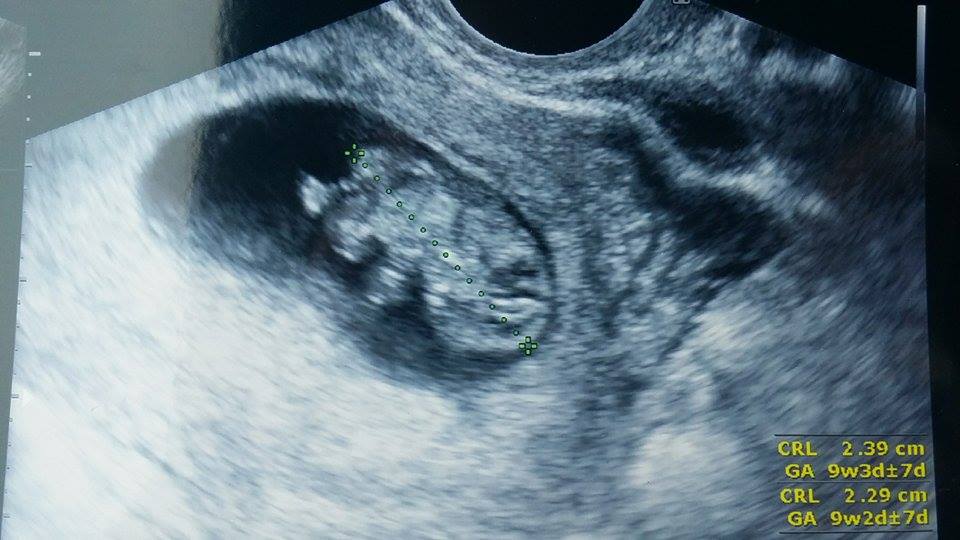

@mastalka já jsem měla pozitivní test 7 dnů po transferu a na utz jsem šla 12 dnů po ET ale ke své gynekoložce, to byla jen zvětšená sliznice, 14 dnů po ET jsem šla znovu na krev na hCG a pak 19 dnů po ET už byla dutinka s embryjkem vidět 😀 Do Unicy si mě zvali až později, tuším jsem čekala ještě další 2 týdny na potvrzení utz a tam jsem poprvé v životě viděla bijící srdíčko. Byla to nádhera. Jako vidět dutinku je fajn, uklidní tě to, že je všechno jak má, ale vidět bijící srdíčko - tomu se dutinka nevyrovná 😉 Těhu příznaky jsem pak už měla, dost mě bolely prsa a bolí doteď (i když ne denně) a bývá mi špatně, ale zvracela jsem jen jednou. Ale už jsem si našla fintu na nevolnosti, takže teď je mi celkem fajn. Ale už než jsem jela na Unicu na utz tak jsem nevolnosti měla. Ale každá z nás to může mít jinak. Co mám já, nemusíš mít ty.